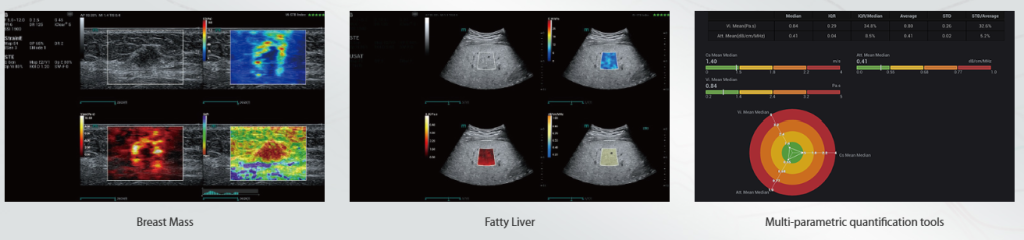

M Reference

M Reference — это инструмент многопараметрического комбинированного анализа, который позволяет проводить диагностику в реальном времени на одном срезе и в одном экране для мультипараметрической ультразвуковой диагностики (MPUS). В отличие от традиционной однотипной ультразвуковой визуализации, он предоставляет многомерную диагностическую информацию и количественные показатели для оценки заболеваний.

-

Мультипараметрический комбинированный анализ

-

Инструменты для количественной оценки

-

Оценка в реальном времени на одном экране

-

Опухоль молочной железы

-

Жировой гепатоз

-

Мультипараметрическая количественная оценка